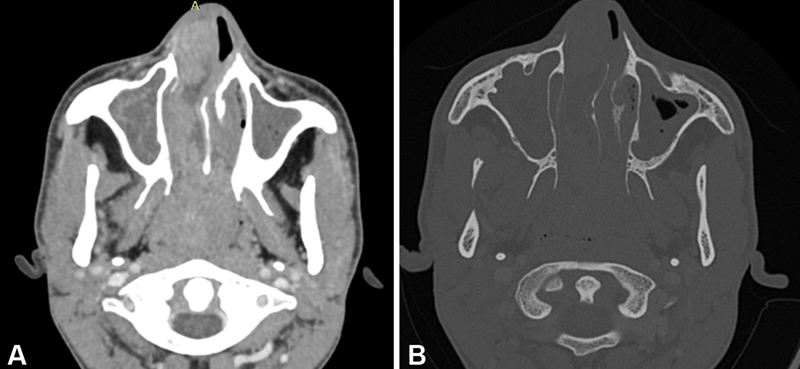

| Figure 4:Sinonasal adenocarcinoma. (A) Axial contrast computed tomographic image in soft tissue window shows irregular lobulated mass in the right nasal cavity protruding as far as the anterior choana, and the nasopharynx. Retained secretions in the maxillary sinus noted. (B) Axial bone window image shows destruction of the right turbinate.